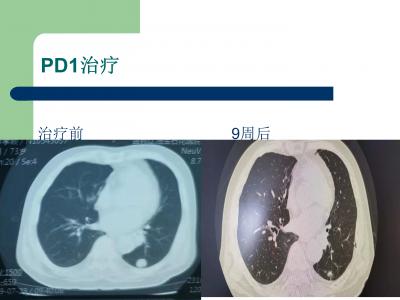

3周后复查、9周后复查左肺下叶肿瘤明显缩小,超声查锁骨上淋巴结也明显缩小,其余病灶略缩小。期间没有出现任何不良反应。患者说得了这么大的病这么重结果糟的罪比感冒还轻!下一步的治疗问题我在学术交流会提出了几个问题,省内专家们给出了解答

当时思考:有长期吸烟病史,肺门附近占位、肺鳞癌可能大。患者高龄,有穿刺风险无法顺利取得病理,征求主任意见:这么多病灶不排除颈部淋巴结转移,复查超声果然左锁上有一个高度怀疑恶性的淋巴结,对这个淋巴结穿刺活检风险就小多了,收入院穿刺准备。穿刺前查PETCT进一步确证为恶性,未发现其他远处转移,SUV平均>30,考虑低分化高度恶性疯长的肿瘤。半个月后穿刺病理:果然是低分化鳞癌,同时做了基因检测很幸运PD-l1:70:% TMB:30.65 /Mb brac1基因突变KEYNOTE-024主要研究终点:帕博利珠单抗单药治疗组的PFS优于化疗组,建议患者单药K药治疗。患者鳞癌不能享受腺癌的赠药政策,充分沟通后因为身体瘦小,选择了信迪利单抗100mg的单药治疗方案。按照经验:老年,肿瘤负荷大,身体不好的患者用PD1治疗效果差、副反应大,容易超进展,但是这个患者的基因检测特别适合免疫治疗,所以充分沟通,家里人不打算化疗,选择相信检测结果,行单药免疫治疗。下药前再次复查CT:肿瘤明显进展,咳嗽加重,乏力加重!结果用药5天后电话随访:患者咳嗽消失,食欲恢复,直接变成了正常人!!!因为高龄,肿瘤分化差,还是给的半量免疫治疗,担心超进展和不良反应。我没有选择9周一复查,而是3周复查一次。